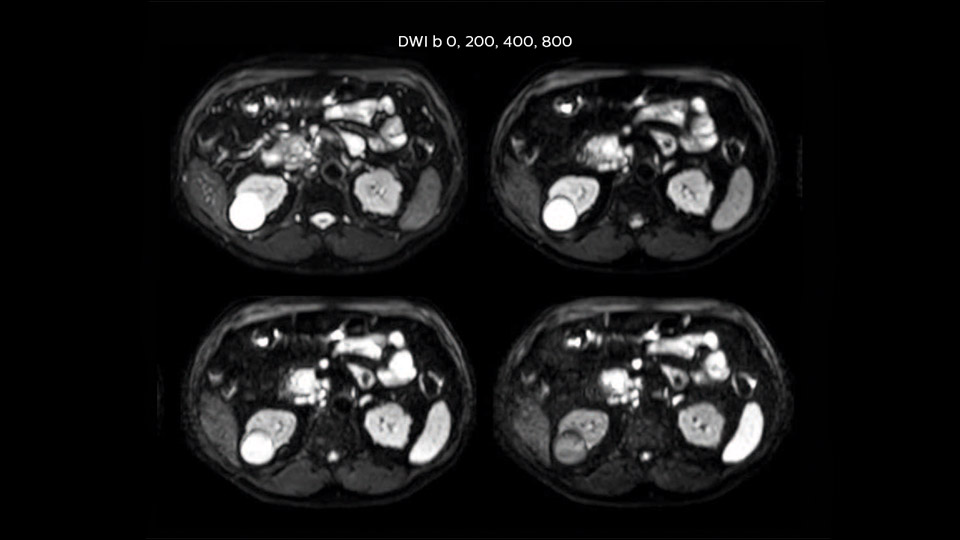

Comparison of liver MRI with and without MultiVane XD motion correction

In this example the image quality of the MultiVane XD images is evidently better than in the images without MultiVane XD. Ingenia 1.5T with dS Torso coil solution.

“We acquire one transversal high resolution T2-weighted sequence with 3 mm slice thickness, for example for pancreas or liver lesions. Then we also add a T2 fat suppressed MultiVane XD SPIR sequence. We perform these two routinely in our liver imaging. We use high dS SENSE factors to significantly shorten scan times to 2-4 minutes, which can improve our protocol; it’s a very robust scan.”